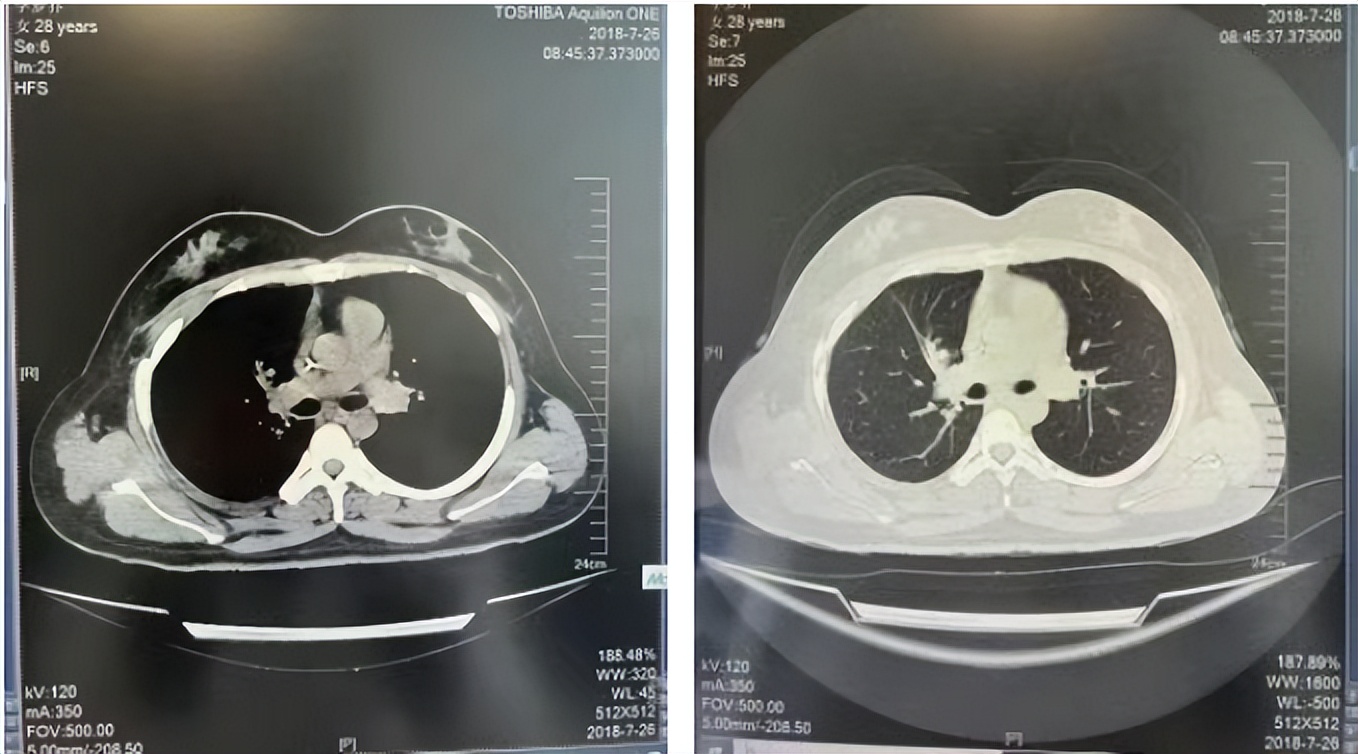

56岁,女性,无吸烟史饮酒史,既往体健。2023年02月患者体检发现肺占位性病变,胸部增强CT:右肺下叶后基底段结节;右侧锁骨上及纵隔内多发淋巴结肿大。PET-CT:右肺下叶周围型肺癌可能性大;1R、2L、3P、4R、4L及7组淋巴结转移可能性大。2023年02月就诊于本院胸外科行超声胃镜下纵隔肿物穿刺活检术,病理:结合免疫组化,符合肺腺癌。行NGS基因检测:EML4:exon20-ALK:exon20融合。PD-L1(克隆号22C3)TPS=55%。

临床诊断:右肺下叶恶性肿瘤cT1bN3M0,IIIB(第9版分期),纵隔淋巴结继发恶性肿瘤,锁骨上淋巴肿继发恶性肿瘤

治疗经过:2023年3月27日始行恩沙替尼靶向治疗至今,最佳疗效为PR,末次评效为维持PR。期间出现轻度肝功能异常(DILI 1级),对症处理后好转。截止目前PFS为26个月。

2023年2月20日基线检查

2024年6月复查PR(最佳疗效)

2024年12月复查维持PR

2025年3月复查维持PR